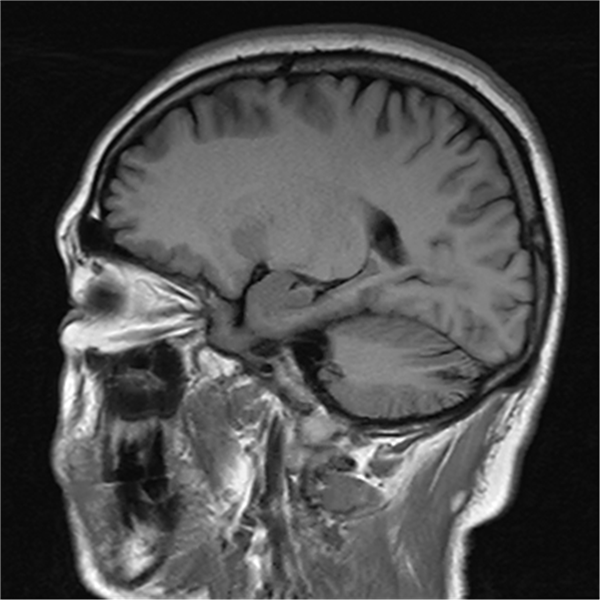

(一)神经系统方面应用:弥散成像(DWI)、灌注加权成像(PWI)及磁共振波谱成像(MRS)的应用,能发现超早期脑中风、脑肿瘤、脑血管畸形(MRA成像)和各种感染性疾病,对癫痫、儿童脑发育不良、创伤及预后、肿瘤术后疗效及有无复发的判断均有良好效果。

部分平扫图像展示